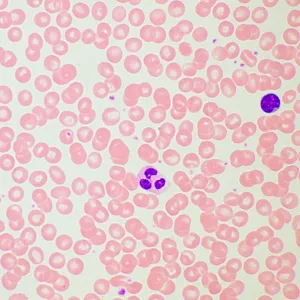

Микроскоп MAGUS Bio 260T – рутинный, с ним можно проводить лабораторные и научные исследования, или использовать его для учебного процесса. Микроскоп работает с тонкими прозрачными и полупрозрачными препаратами в светлом поле. Однако на прибор можно поставить дополнительные компоненты, которые расширят его возможности для проведения исследований по методам темного поля, фазового контраста, в поляризованном и люминесцентном свете.

Дополнительные элементы расширят функционал прибора. Набор окуляров увеличит спектр увеличения. Для дополнительных методов работы с препаратами, которые невозможно рассмотреть в светлом поле, нужно дополнить микроскоп фазово-контрастным устройством, слайдером темного поля или устройством простой поляризации. Цифровая камера поможет зафиксировать на фото или видео результаты исследования или выведет картинку на экран. Измерить объекты можно, применяя калибровочный слайд вместе с окуляром со шкалой или с цифровой камерой.